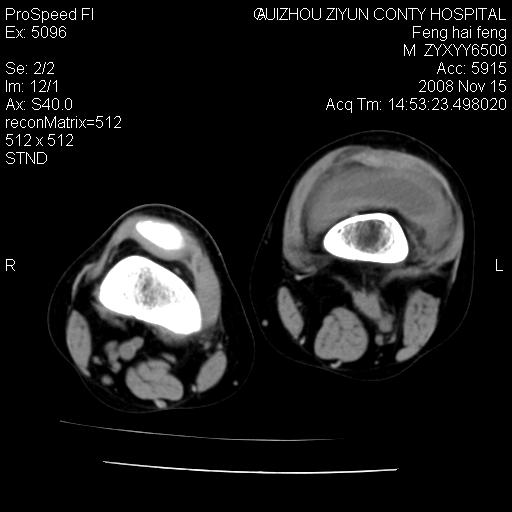

标题: CT16656:M 14Y 左膝关节肿胀一年余。其余病史不详。 [打印本页]

标题: CT16656:M 14Y 左膝关节肿胀一年余。其余病史不详。

考虑左侧髌骨结核;左膝关节滑膜肿胀、增厚,关节囊积液。

左膝滑膜型关节结核可能性大!支持!滑膜型关节结核主要ct表现:关节囊肿胀,积液,关节面见小破坏灶,并见点状死骨!

好大的左腿!考虑左侧髌骨结核,左膝关节滑膜肿胀、增厚,关节囊积液。

左侧髌骨结核;左膝关节滑膜肿胀、增厚,关节囊积液